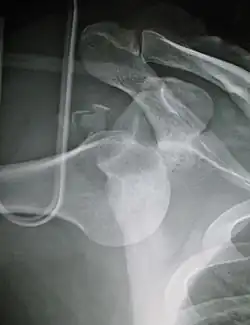

| Anterior dislocation of the left shoulder. | |

In over 95% of shoulder dislocations, the humerus is displaced anteriorly.[8] In most of those, the head of the humerus comes to rest under the coracoid process, referred to as sub-coracoid dislocation. Sub-glenoid, subclavicular, and, very rarely, intrathoracic or retroperitoneal dislocations may also occur.[9]

Anterior dislocations are usually caused by a direct blow to, or fall on, an outstretched arm. The person typically holds his/her arm externally rotated and slightly abducted.[10]

- An anterior dislocation of the shoulder

Anterior dislocation of the right shoulder. AP X ray -